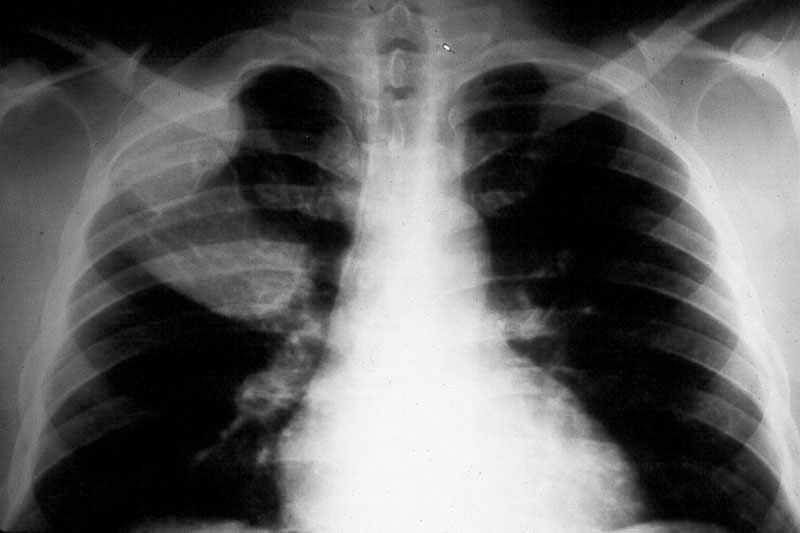

Bony thoracic cage In the bony thoracic cage the ribs are frequently affected (Figure 7).

Figure 7: FD – note the expanding lesions of the right 1st and 2nd ribs.